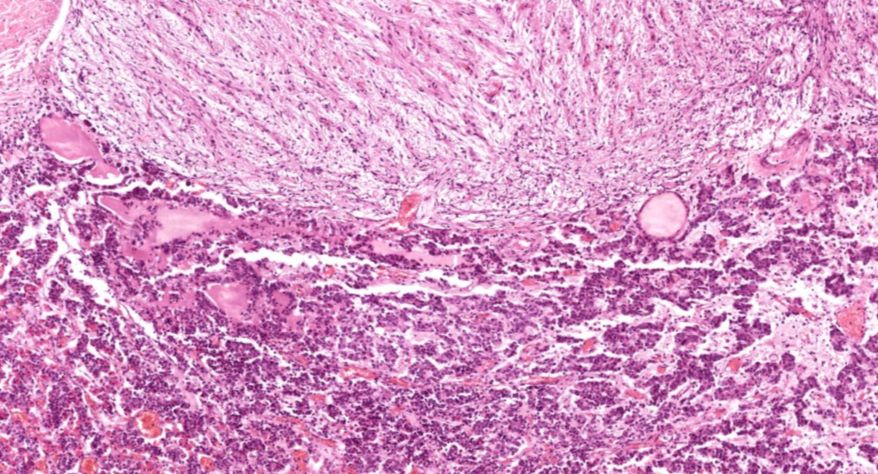

低倍镜:分出皮质及髓质。皮质由表至里分为三个带:高倍镜:(1)皮质:①球状带的细胞聚集成球状团块,细胞较小,矮柱状或多边形,核小,着色深,胞质弱嗜碱性,有少量脂滴。②束状带很厚,细胞排列成束状,在细胞之间有少量结缔组织及丰富的血窦,高倍镜观察束状带的细胞体积较大,呈多边形,核大而着色浅,胞质有许多脂滴,在制片过程中被溶解,因此胞质染色很淡。③网状带细胞排列成索,细胞索互相吻合成网,索间有丰富的血窦,胞质染色略呈嗜酸性,脂滴很少,核小着色浅。(2)髓质:髓质和皮质交界参差不齐,髓质细胞较大,呈多边形,此外还有少量交感神经节细胞,后者胞体较大,胞质着色浅,常单个或2~3个成群散布于髓质内。

1.全景图

2.被膜

3.皮质

4.球状带(10x)

5.球状带(40x)

6.束状带(10x)

7束状带(40x)

8.网状带(10x)

9.网状带(40x)

10.网状带细胞内脂褐素

11.髓质

12.嗜铬细胞

13.交感神经节细胞

14.中央静脉